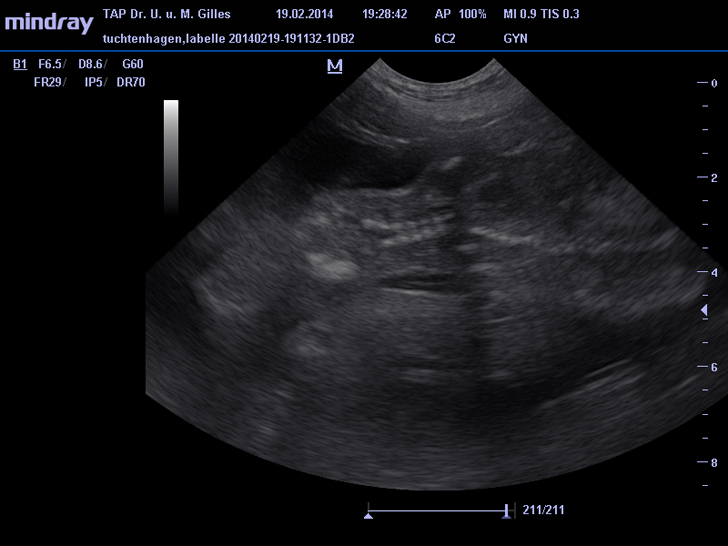

Neuer Ultraschall vom 19.02.2012 (42. Tag):

Alle kleinen Hunde-Embryos leben und haben sich prächtig entwickelt.

ZZt. sind sie schon ca. 7 cm groß.